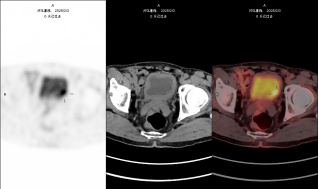

blob.pngblob.png

图注:左图为常规显像、右图为延迟显像,延迟显像明确膀胱壁占位。